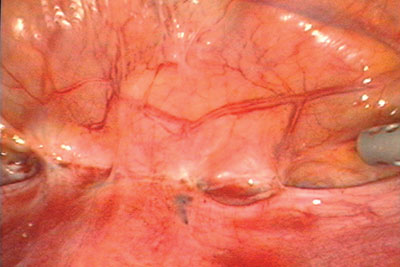

Figure 1. Les lésions symptomatiques d’endométriose du diaphragme (voir flèches) sont habituellement situées sur la partie postérieure de l’hémidiaphragme droit. Cette zone n’est pas facile à explorer à l’aide du laparoscope introduit par le nombril, mais est toujours visible lorsqu’on utilise un laparoscope de 5 mm avancé à travers la gaine musculaire située au-dessous du rebord costal droit, comme on peut le voir ici.

Figure 2. L’endométriose du cul de sac vaginal postérieur a provoqué un amas épithélial (voir l’intérieur du cercle). Une endométriose vaginale peut être associée à une obstruction du cul de sac de Douglas et résulter d’une extension invasive de la maladie qui va des ligaments utéro-sacrés ou d’un nodule rectal vers le vagin.

Figure 12 : Le rectum est légèrement arrondi (flèche) à l’endroit où il rejoint le ligament utéro-sacré droit. Cette forme arrondie montre que la paroi rectale est atteinte d’endométriose et nécessitera une forme de chirurgie digestive pour enlever complètement le foyer. Le cul de sac à gauche du rectum montre des lésions glandulaires superficielles d’endométriose entourées de cicatrices stellaires.

*

Figure 13 : La paroi postérieure de l’utérus montre plusieurs taches hémorragiques représentant soit une adénomyose, soit une endométriose avec une néovascularisation contiguë. L’exérèse de l’endométriose ne soignera pas les symptômes utérins révélés par ces découvertes et qui ne sont pas dus à l’endométriose. Le cul de sac est complètement obstrué, mais la paroi rectale est lisse, ce qui indique qu’il y a très peu où pas d’endométriose rectale. L’ovaire gauche est kystique et caché sous des sinuosités péritonéales accolées au ligament utéro-sacré gauche. Des lésions glandulaires superficielles d’endométriose touchées par une fibrose légère peuvent être observées sur le ligament large droit.